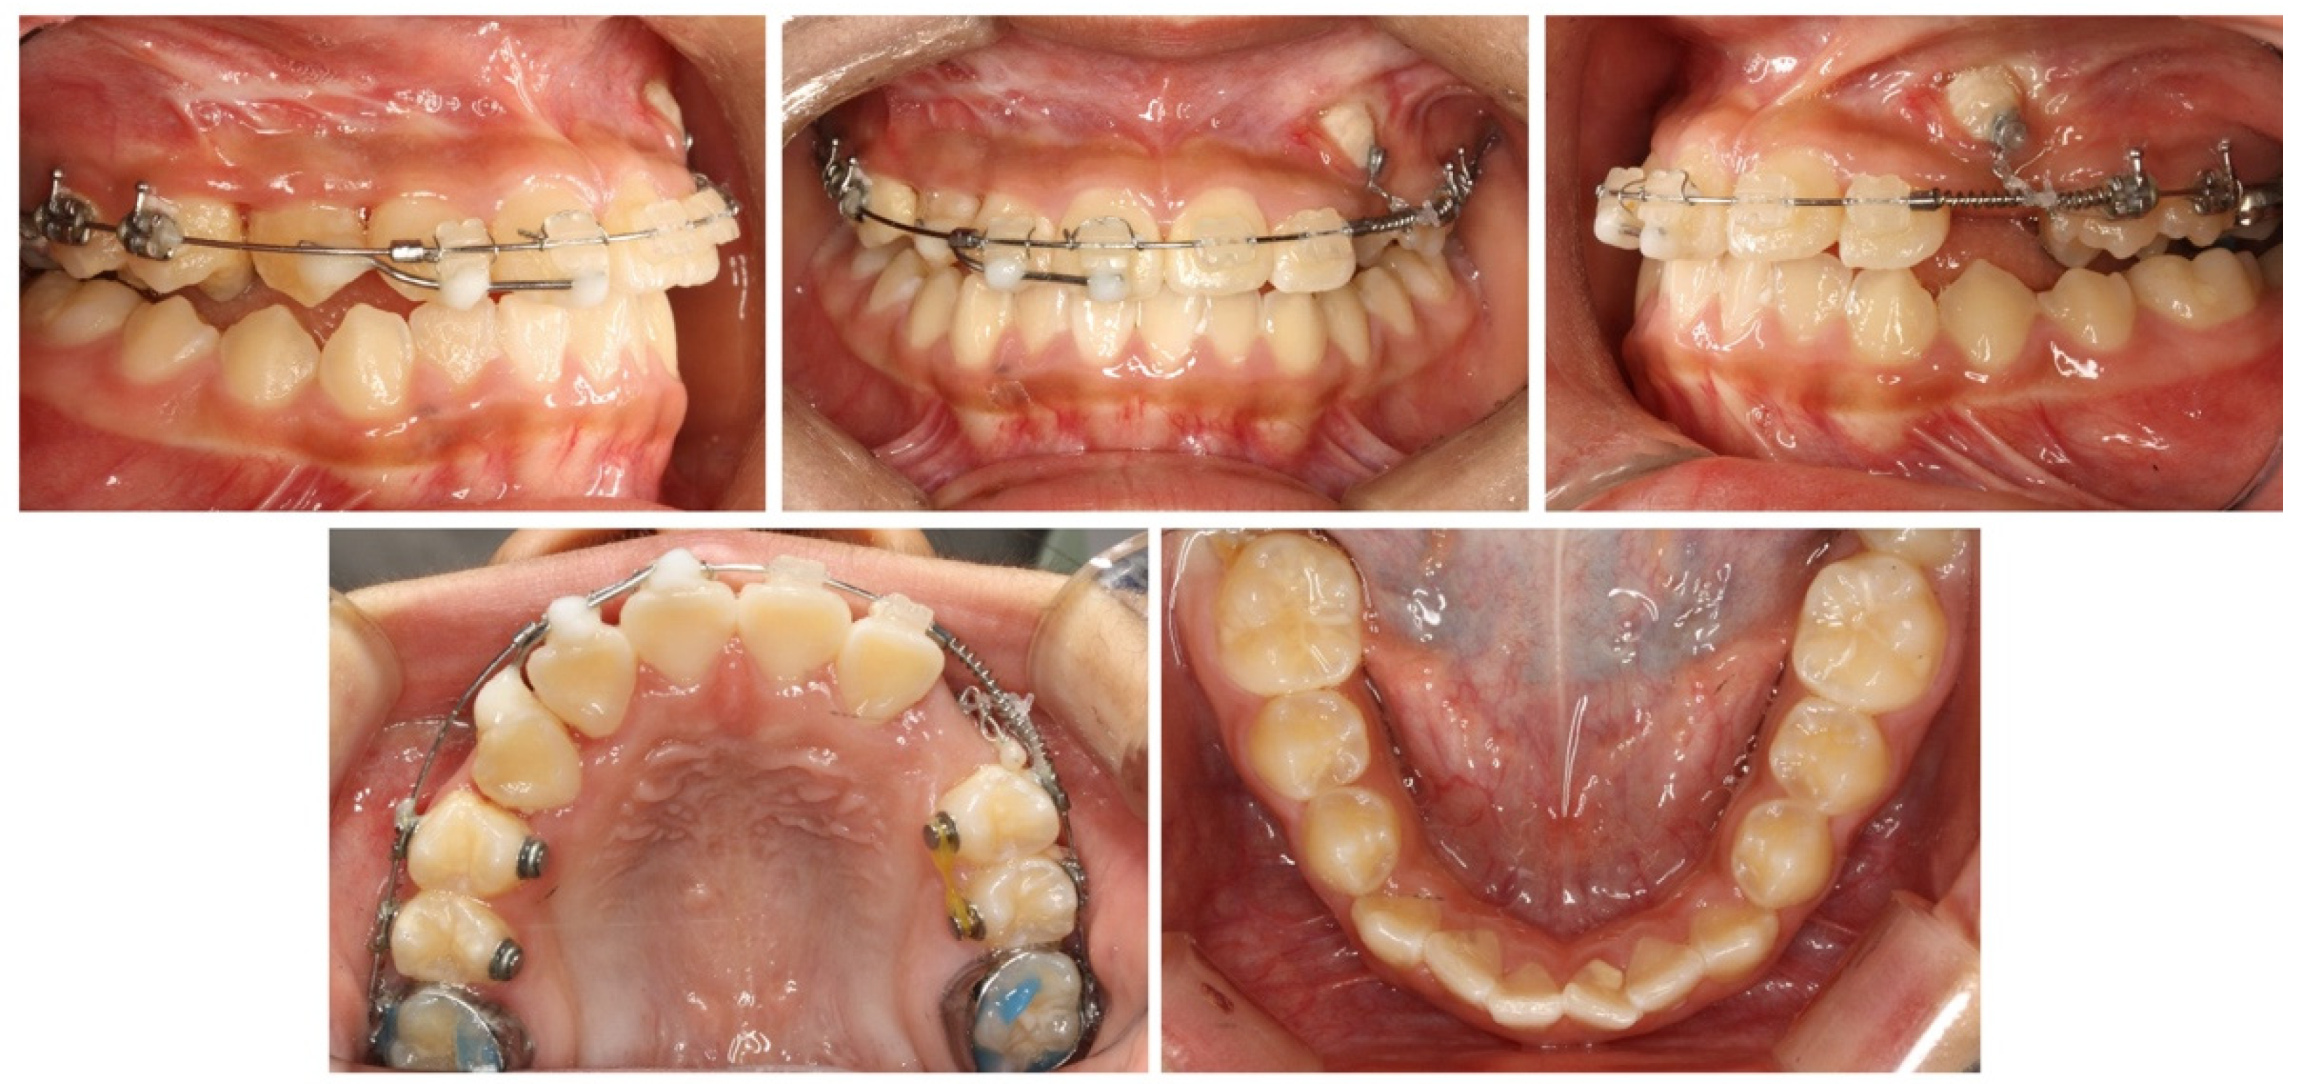

2.4. Treatment Progress

2.5. Treatment Results